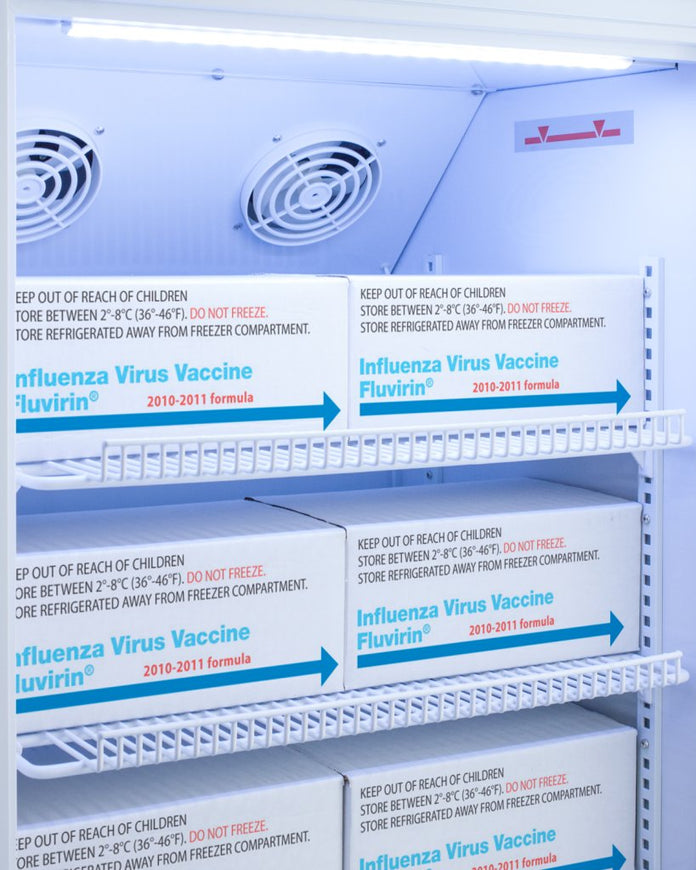

Inside, the ARS6PV-CRT utilizes adjustable cycle defrost operation to avoid temperature spikes. Optimized forced air cooling with an internal fan ensures excellent temperature stability and uniformity with rapid recovery after door openings. The adjustable plastic-coated wire shelves can be positioned at 1/2" increments to accommodate virtually any sized item. This unit includes LED internal lighting with an on/off rocker switch. The interior is constructed from white powder coated metal to ensure added durability and better temperature retention.

Designed with hydrocarbon refrigerant, the ARS6PV-CRT provides an energy efficient solution to stabilized room temperature storage, even when ambient temperatures can reach temperatures as cold as 68ºF or warm as 86ºF. This unit is Pyxis, Omnicell, and AcuDose RX compatible. Additional sizes, as well as glass door options, are also available.